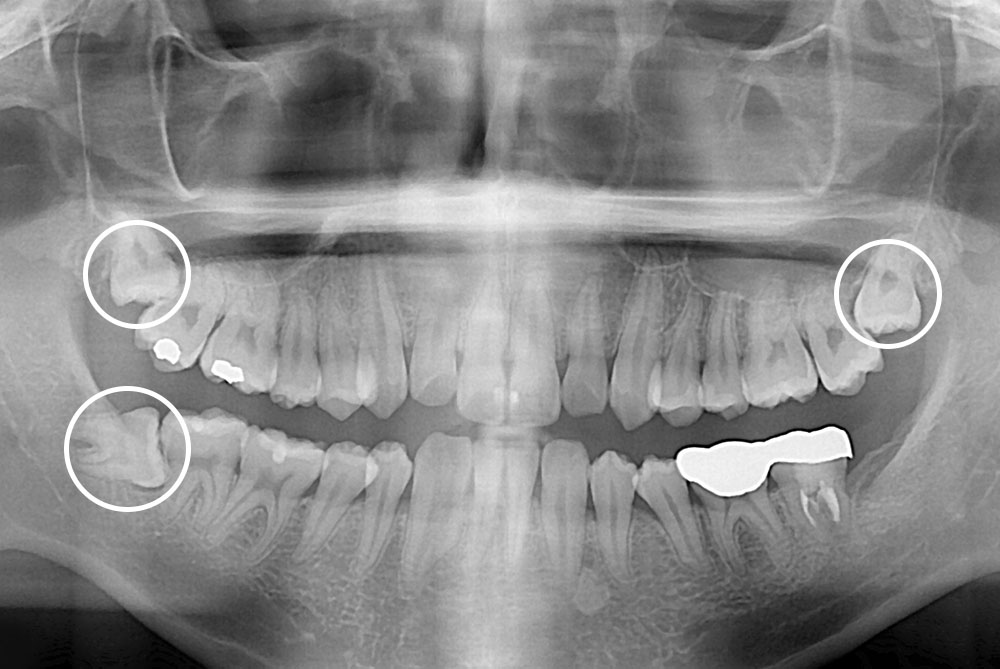

[사랑니] 매복 사랑니 발치

치료전 : 2018-04-25